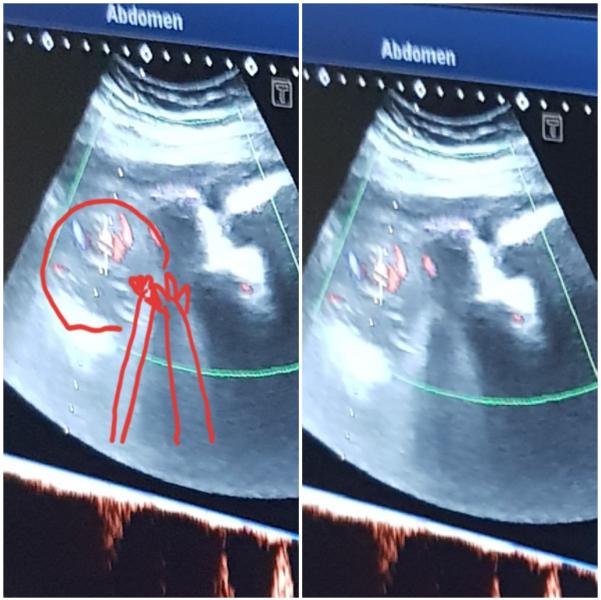

@viktoria_v_teme, в том то и дело постоянно смотрела по узи и доплер был...никто ничего не сказал и не увидел

@verysik88_88 мдаааа... хотя может он обвился в последний момент.